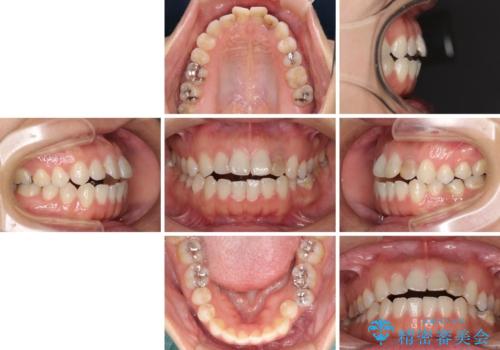

開咬と変色した前歯 インビザライン矯正とオールセラミッククラウン治療

- 前歯の開咬と失活により変色した前歯を気にして来院された患者様です。

開咬の治療は、前歯を閉じるように引っ張り出すよりも、上下臼歯を圧下(骨内にめり込ませる)させることで進める方が長期的に安定した歯列を維持できます。

インビザラインは臼歯の圧下を効果的に行えるため、インビザラインを用いて矯正治療を行うこととしました。

矯正治療が概ね終了した時点で前歯をオールセラミッククラウンにて補綴治療を行い、その後インビザラインにて細かい部分を仕上げていくことしました。